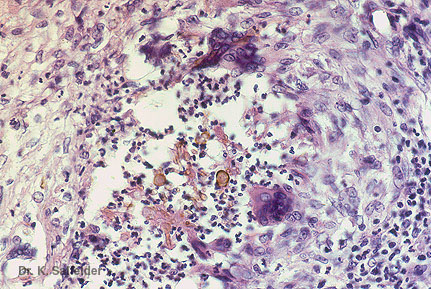

Abb. 13,19: Phaeohyphomykose

Gelbe Hyphen sind in diesem Fall kaum zu erkennen. In der Peripheie des Abszesses Riesenzellen. HE-Faerbung